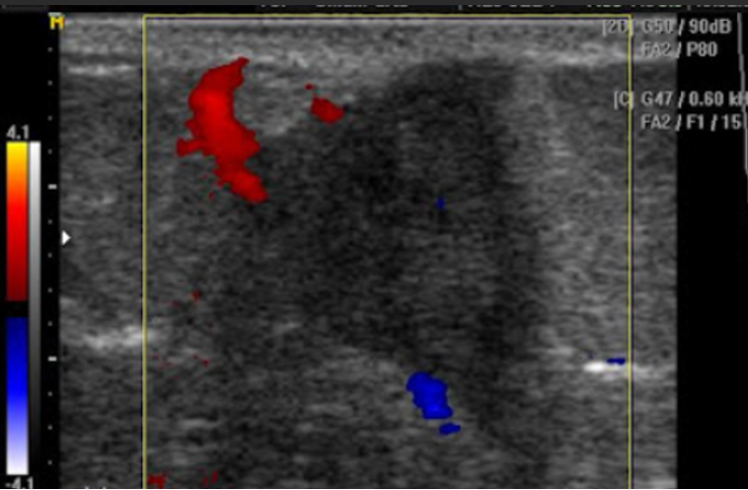

•  Tumors

•  Lesions

•  Abnormal growth

•  Aneurysms

This screening can help identify abnormalities such as tumors, cysts, or vascular issues at an early stage, potentially improving treatment outcomes. Our general screening exams include: breast, thyroid, kidneys, liver, spleen, aorta, pancreas, and calf veins.